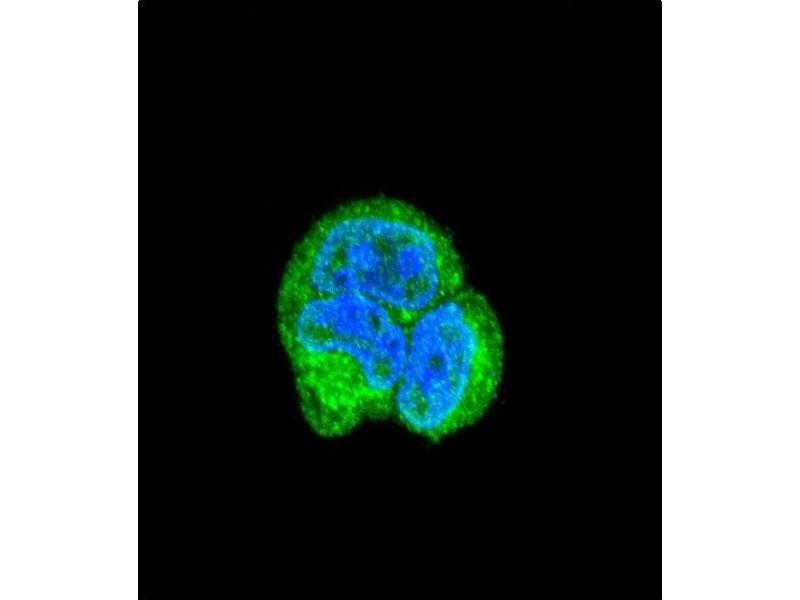

ASPA Antikörper (N-Term)

Der Kaninchen Polyklonal anti-ASPA Antikörper (Klon RB20918) (ABIN390843) detektiert spezifisch ASPA in WB, IF, IHC (p) und FACS. Dieser Antikörper reagiert spezifisch mit Proben aus Human.

Western Blotting (WB), Immunofluorescence (IF), Immunohistochemistry (Paraffin-embedded Sections) (IHC (p)), Flow Cytometry (FACS)

This ASPA antibody is generated from rabbits immunized with a KLH conjugated synthetic peptide between 82-110 amino acids from the N-terminal region of human ASPA.

IF: 1:10~50. WB: 1:1000. WB: 1:1000. IHC-P: 1:50~100. FC: 1:10~50